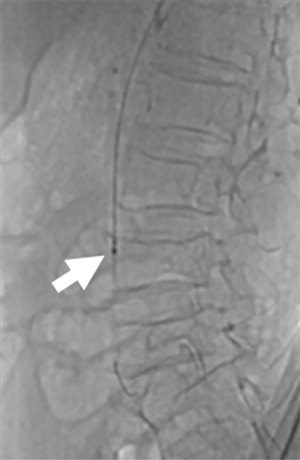

A 73-year-old woman was admitted to hospital due to abdominal pain for 20 h. She had a history of rheumatic heart disease and atrial fibrillation, and did not receive anticoagulation therapy. No other abdominal signs were found except periumbilical and lower abdominal tenderness and absence of bowel sounds. The vital signs were normal. The electrocardiogram showed atrial fibrillation, and CT angiography of the entire abdomen showed filling defects in the middle and distal superior mesenteric artery (Figure 1). Laboratory tests showed a white cell count of 20.44×109/L, and normal coagulation profile and liver and kidney functions. Consultation of a general surgeon confirmed that no signs of intestinal necrosis were found. After informed consent was obtained, the patient underwent immediate emergency interventional surgery.

The patient lied in supine position. The left arm was put on the abdomen with natural internal rotation, and the left hand was placed toward the patient’s right groin, followed by disinfection. 2 mL of lidocaine was injected into the left anatomical snuff box, and a 21 G puncture needle was inserted at an angle of 35–45 degree into the radial fossa where the pulse was the strongest. After successful puncture, a 0.25-inch J-shaped guide wire was slowly inserted, and a 6 French radial artery sheath (Braidin, APT) (Figure 2) was inserted following skin incision. 3,000 U heparin was administered. Under the guidance of the loach guide wire, a 4 French ULTIMATE1 catheter (1,250 mm) was placed at the opening of the superior mesenteric artery. Angiography showed a filling defect of approximately 5 cm in the middle and distal portions of the main trunk of the superior mesenteric artery, and the distal arteries were well visualized (Figure 3). A 0.018 guide wire was inserted into the distal branch of the superior mesenteric artery, and 6 French Rotarex rotational excisional system (1,350 mm) was introduced along the guide wire (Figure 4). The thrombus was slowly suctioned from the distal to the proximal end twice. The main trunk and branches of the superior mesenteric artery were well visualized on repeated imaging. No obvious residual thrombus was observed, and distal blood flow was normal (Figure 5). 200 µg of Nitroglycerin was injected into the sheath, which was then removed, and a pressure bandage was applied for 3 h. The operation was successful and the patient did not experience noticeable discomfort. The total operation time was 40 min, and the Rotarex mechanical rotational excisional system was used for around 1 min.